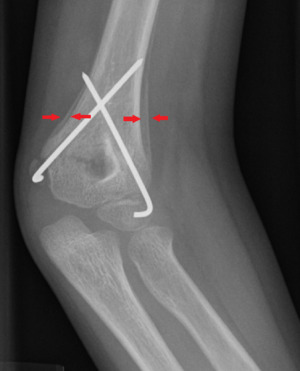

Periosteal reaction on a healing supracondylar fracture

A periosteal reaction is the formation of new bone in response to injury or other stimuli of the periosteum surrounding the bone.[1] It is most often identified on X-ray films of the bones.